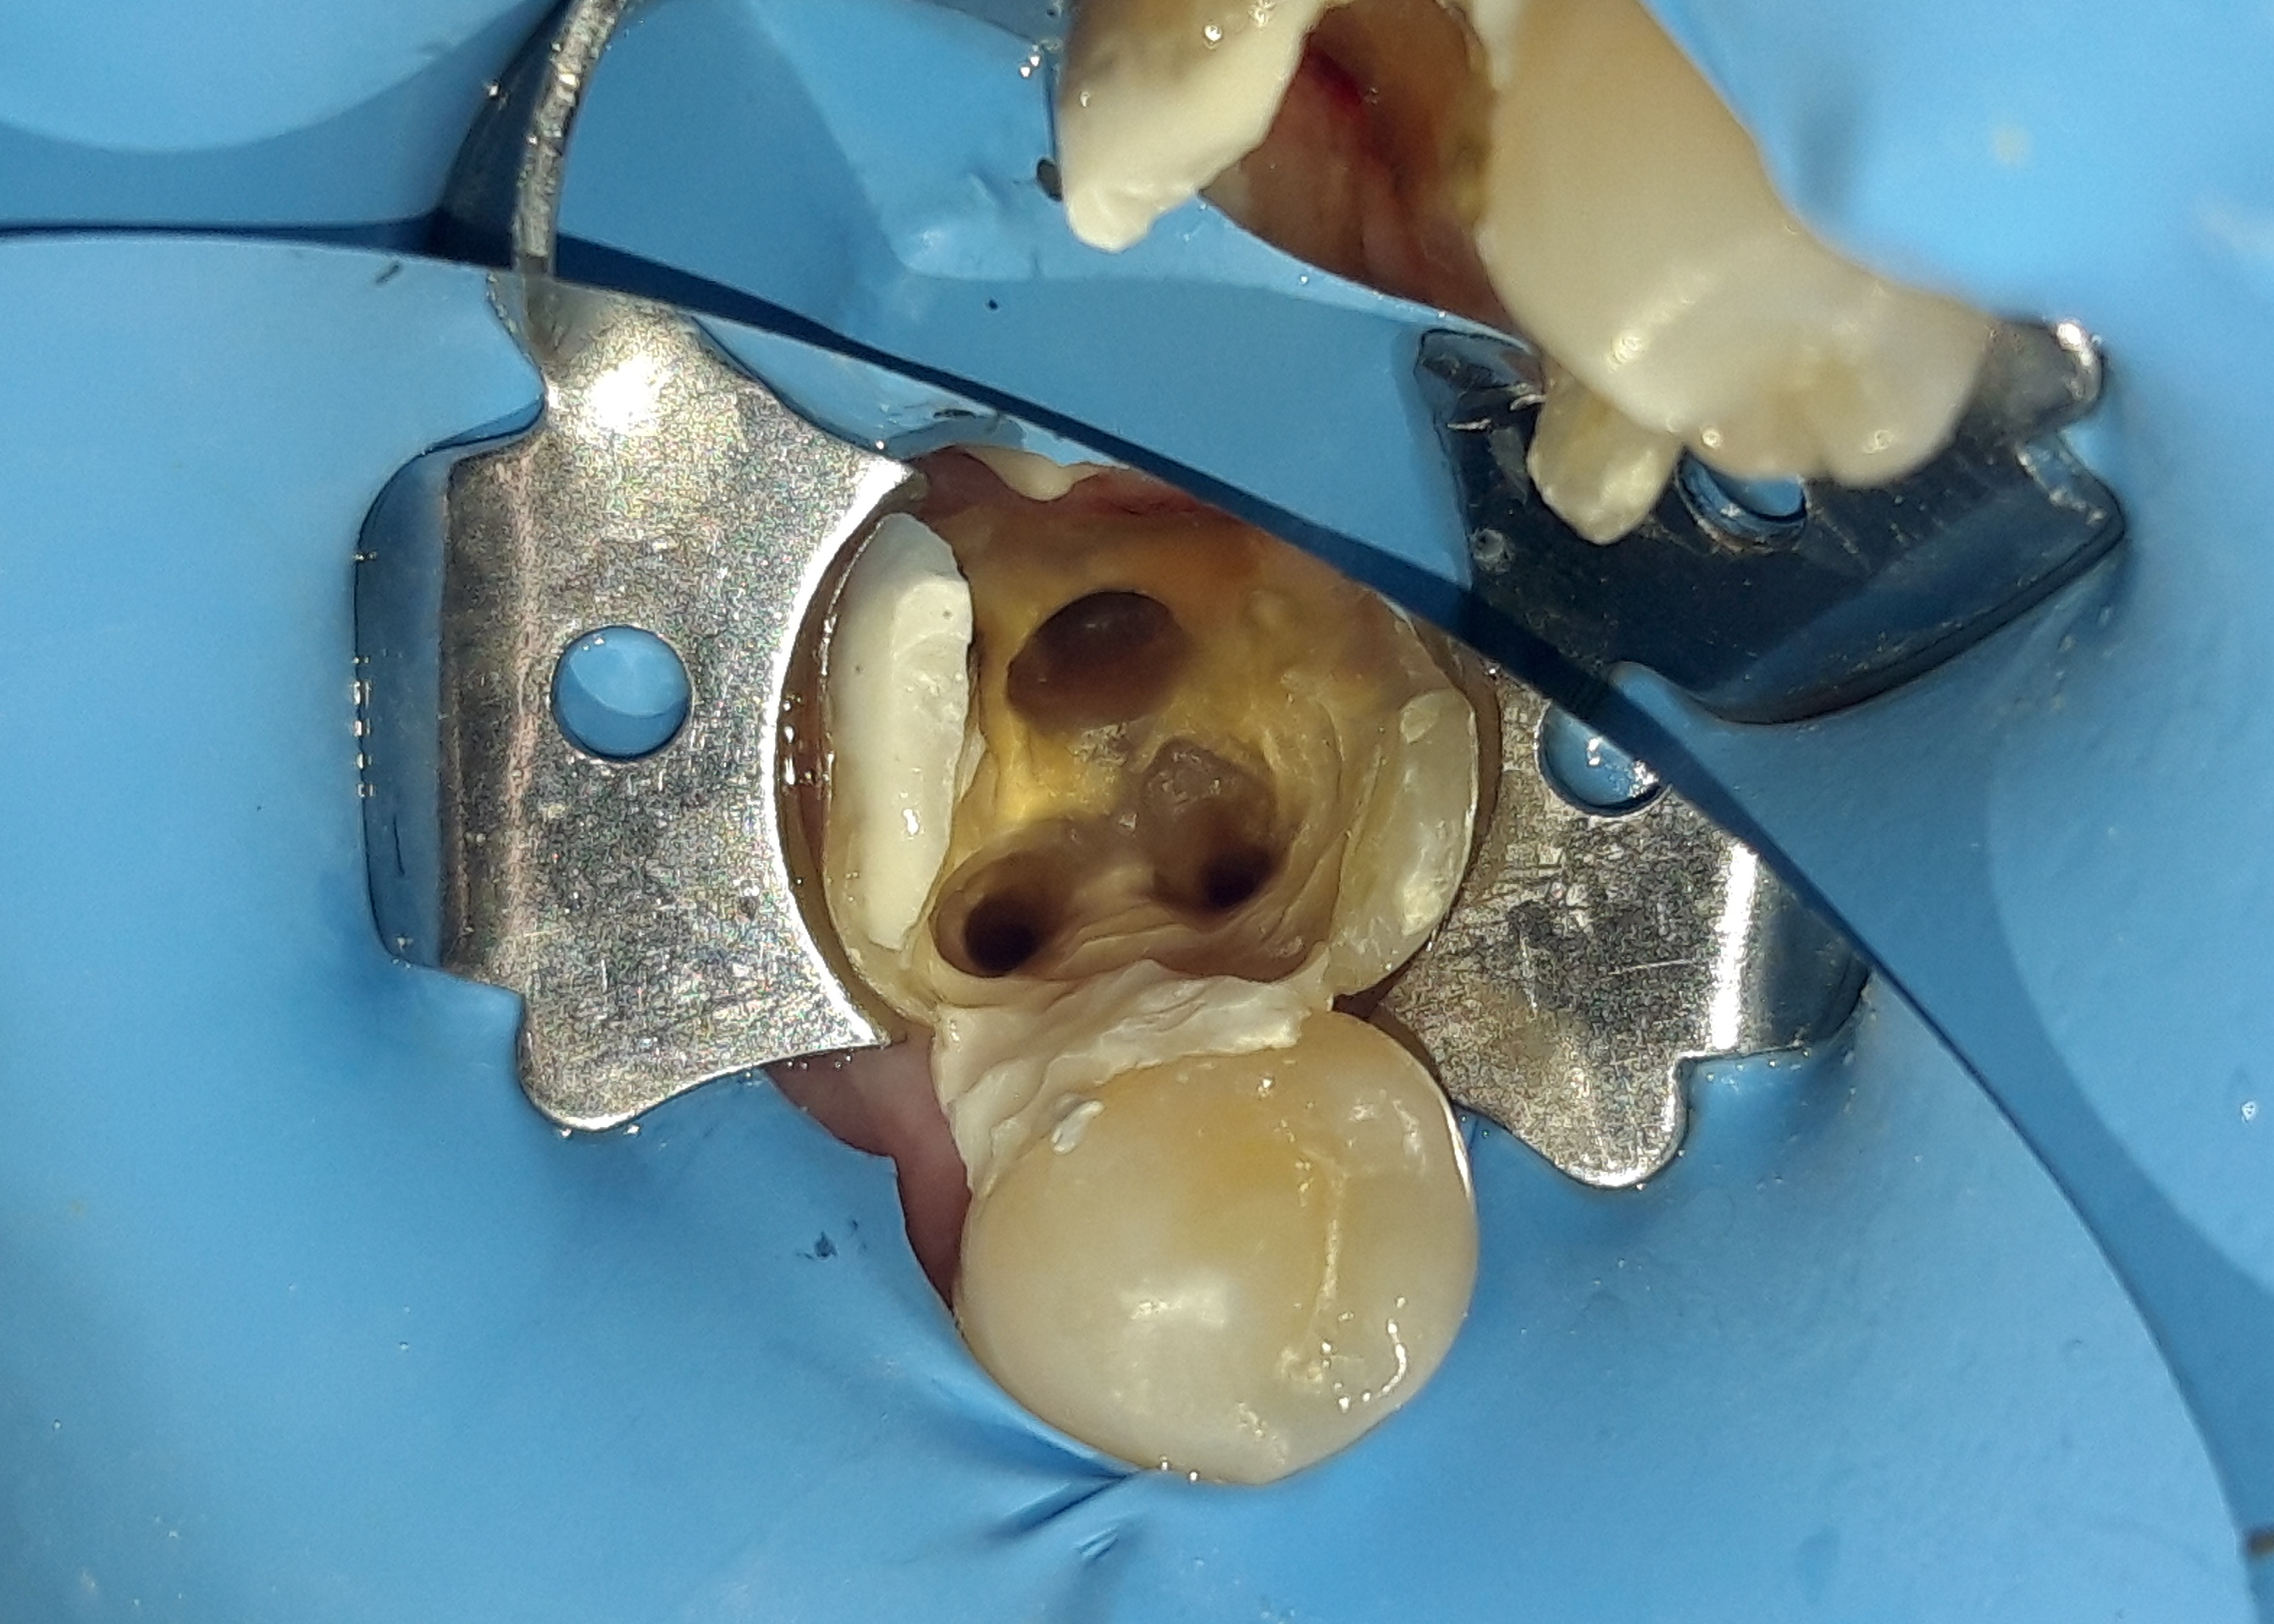

Αρχική εικόνα αμέσως μετά τη διάνοιξη του δεύτερου γομφίου, όπου φαίνονται οι στενοί ριζικοί σωλήνες

Τελική εικόνα των διευρυμένων ριζικών σωλήνων

Τελική εικόνα της απονεύρωσης του δεύτερου γομφίου